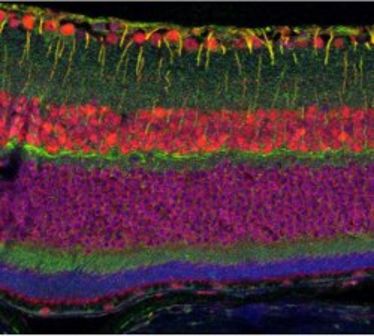

Prof. Willi Halfter: "The biology of ocular basement membranes", Vortrag an der Augenklinik

Prof. Willi Halfter: "The biology of ocular basement membranes", Vortrag an der Augenklinik